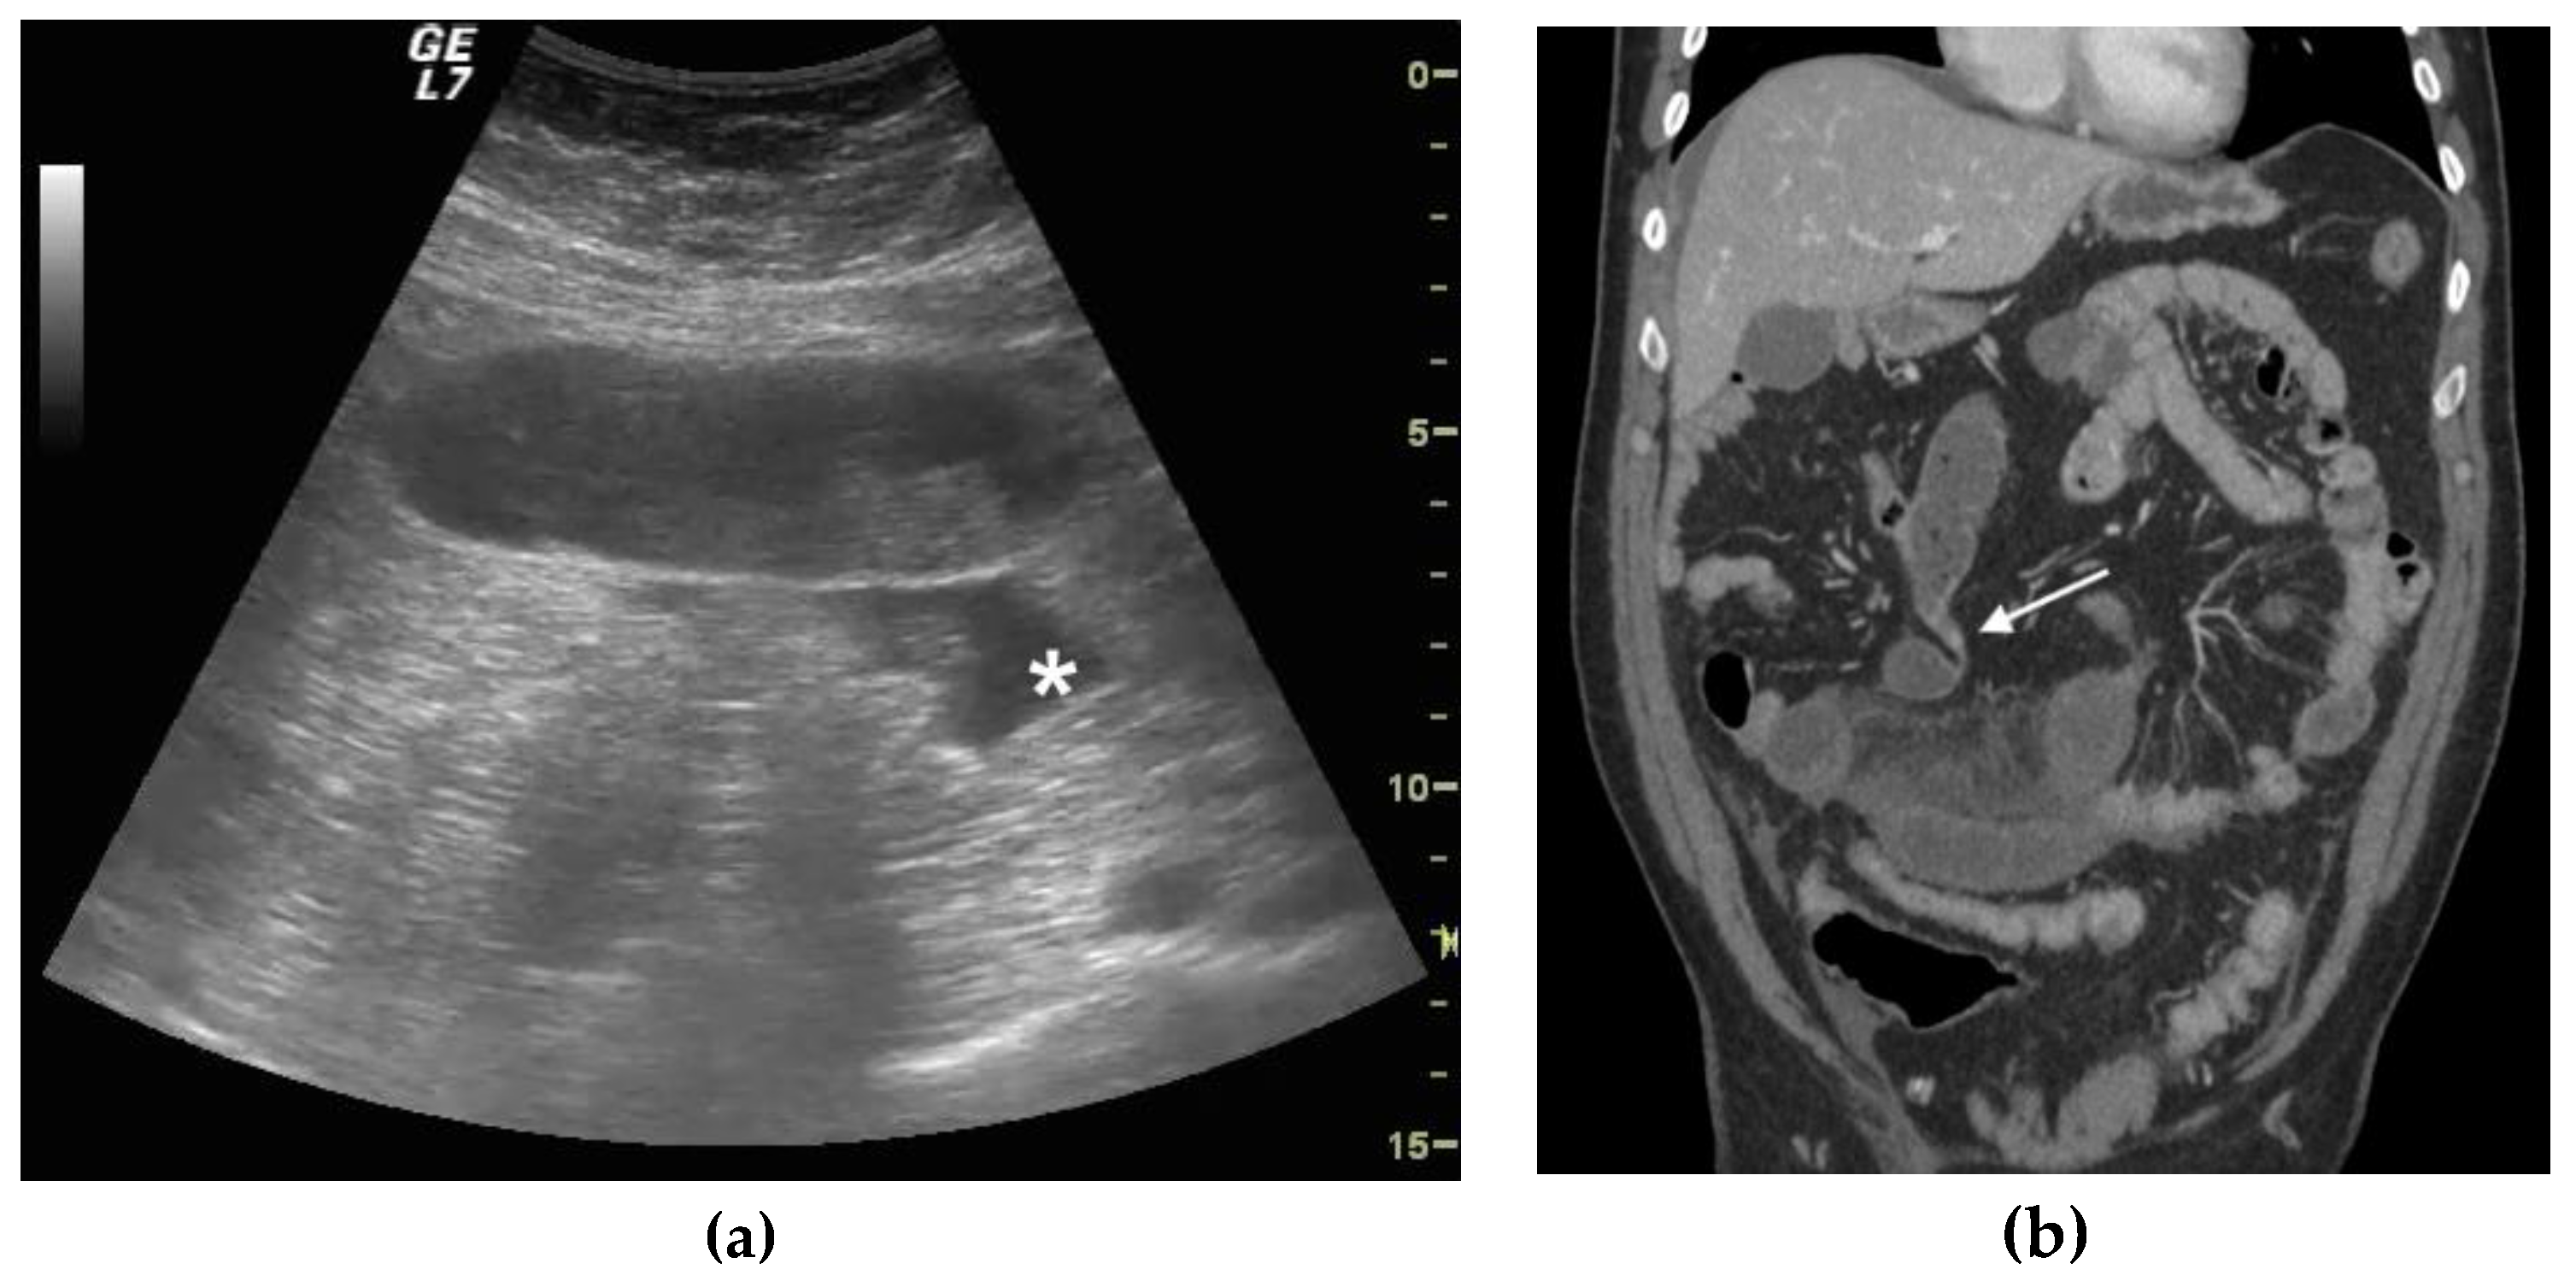

Usg Abdomen Showing Clumped And Matted Small Bowel Loops Forming A Download Scientific Diagram

Diagnostics Free Full Text Diagnostic Accuracy Of Ultrasound In The Diagnosis Of Small Bowel Obstruction Html